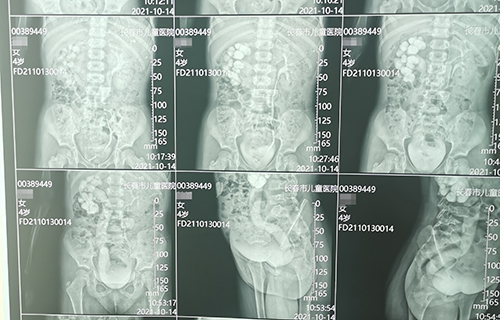

长春4岁女宝佳佳(化名)间歇性腹痛1个月,诊断为输尿管末端狭窄。这种病在儿童中发病率仅为5‰,但危害却不容小觑,长期发展会导致患侧泌尿系扩张积水,影响肾功能甚至导致肾衰竭。故一旦确诊需尽早手术治疗。那么,佳佳到底怎样了呢?

术前准备完毕。10月15日,栾志勇主任、谢方达副主任为佳佳行输尿管远端狭窄微创手术,在其肚脐周围打了3个直径5mm的小孔,在腹腔镜下顺利实施了输尿管膀胱再植。手术用时仅为3小时,出血量也比较少。

佳佳复查彩超,手术效果良好,达到出院标准。10月22日,佳佳就可以回家了。截止到目前,此类微创手术已完成8例。